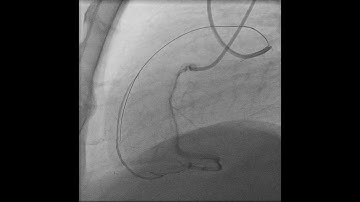

Below the Knee CTO: Antegrade Wire Escalation Algorithm - February 28, 2018